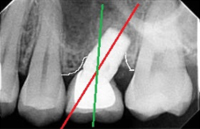

This patient’s existing old partial denture became loose after one of her teeth had broken. After thorough dental examination Dr. Andrews recommended to extract remaining lower teeth and immediately place two regular size dental implants in order to stabilize a new full lower denture.

During only one surgery three lower teeth were removed, two dental implants were placed. Three months later two snap-on attachments were placed on the integrated implants.